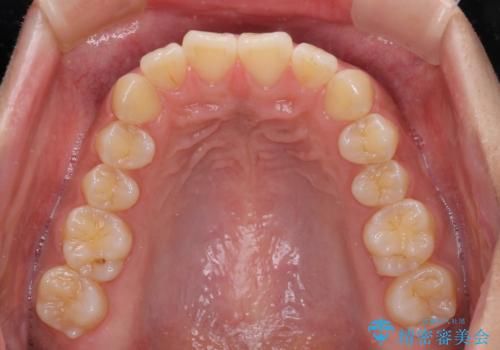

くちばしのような前歯 抜歯矯正で口を閉じやすく

- 前歯の突出感を気にして来院された患者様です。

咬合力が非常に強く、咬合力で前歯が前方に押し広げられており、上下唇に閉じにくさが認められました。

上下左右の第一小臼歯4本を抜歯し、ワイヤー装置にて矯正治療を行うこととしました。

強い咬合力により前歯の隙間がなかなか閉じられず、治療期間は長いものとなりましたが、横顔の印象が大きく変わるほど口元の印象を改善することができました。